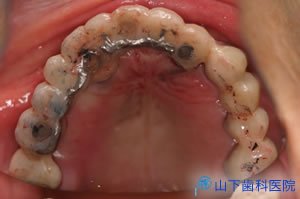

| 「入れ歯」では思うように噛めず、気持ち悪い。前歯で噛んでいるがぐらぐらしてきた。 残る歯もすっきりしない所が多々あり、今後に不安を抱えて来院されました。 |

| 初診時のレントゲン写真です。 | ![]() |

| 上下の奥歯が咬み合うことで決まる咬合が不安定で、下の前歯が上の前歯を突き上げています。 予知性がない右下、左上の4番目を抜歯して落ち着いた状態です。 |